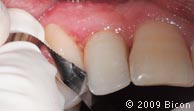

55. Производится полировка интегрированной коронки с помощью акрилового диска.